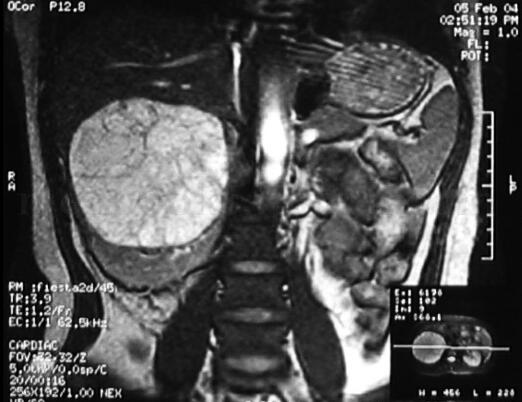

MRI:右肾上极类圆形囊实性占位,呈T1低,T2高,内部信号不均匀,可见散在T2低信号的分隔,肾下极受压成新月形,肝脏受压上移。腹膜后未见肿大淋巴结(图2)。

图2 MRI